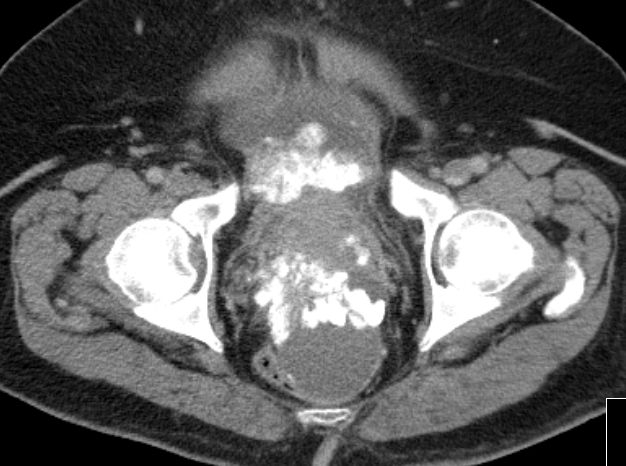

| Fall 1 | 51-jährige Frau mit primärem Peritonealkarzinom. | |||

| Therapie: Partielle Peritonektomie, HE mit Adnexen, Sigmaresektion (Hartmann), Omentumresektion. | Histologisch: Gut differenziertes seröses Adenokarzinom mit massenhaft Psammomkörperchen (Psammokarzinom). G1.Staging: pT3c. | |||